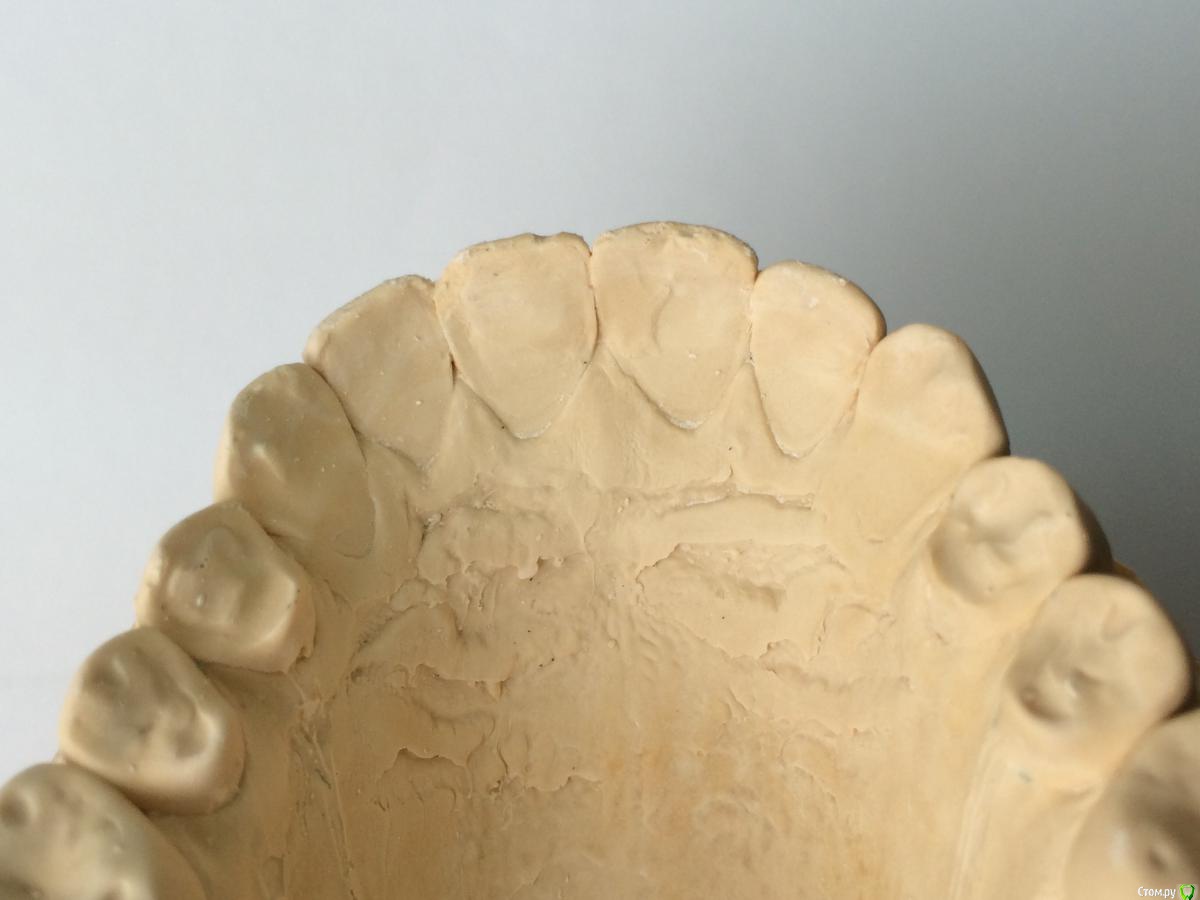

Larnary Опубликовано 28 июля, 2015 Поделиться Опубликовано 28 июля, 2015 (изменено) Добрый день!Ко мне обратилась пациент 1988 гр с жалобой на стираемость зубов и постоянные сколы пломб.Объективно небная поверхность верхних резцов стерта до дентина. Окклюзионная стираемость жевательной группы зубов.Прошу помочь с выявлением причины такой стираемости зубов и оптимальноно метода лечения Изменено 28 июля, 2015 пользователем Larnary Ссылка на комментарий

Larnary Опубликовано 28 июля, 2015 Автор Поделиться Опубликовано 28 июля, 2015 (изменено) Видно окклюзионнык интерференции в области 37 и 47.На днях удален 38 и дальше будут удалены остальные восьмерки. На ТРГ мне видится небольшая ретрузия верхних резцов,дистальный прикус. Так же левпя окклюзионная кривая более выраженная,чем правая Изменено 28 июля, 2015 пользователем Larnary 1 Ссылка на комментарий

Maverick Опубликовано 9 августа, 2015 Поделиться Опубликовано 9 августа, 2015 (изменено) Думаю в данном кейсе интрузия резцов будет нежелательна, десневые контуры фронтальной группы зубов выглядят хорошо, ровно, нет разницы в высоте(если конечно не были внесены изменения в контур десны, типа пластик) . И тут не дентальный глубокий прикус, а скелетный, как было отмечено выше. Еще один негативный момент в интрузии, который играет важную роль , так это искусственное состаривание пациента, верхняя губа имеет свойство опускаться со временем, что только ухудшит картину эстетики улыбки. Экспозиция резцов очень важный критерий в планировании лечения, тут надо отталкиваться от возраста пациента. Думаю у данного пациента, учитывая возраст, позицию фронтальных зубов , уровень десны идеально будет завысить прикус в боковом отделе и вывести в небольшой вестибулярный наклон фронт на брекетах, либо как упоминалось выше за счет изменение наклона коронковой части, путем керамических реставраций, что удобнее для пациента в плане финансовых и временных затрат. P.S. Такое ощущение , что есть определенные проблемы с клыковым ведением, поэтому и интерфреннции возникают в боковом отделе. Поэтому хорошо было бы увидеть все в артикуляторе, чтобы уже точно знать причину Угол межрезцовый идеальный 132 градуса плюс минус 10 град. Изменено 9 августа, 2015 пользователем Maverick 2 Ссылка на комментарий